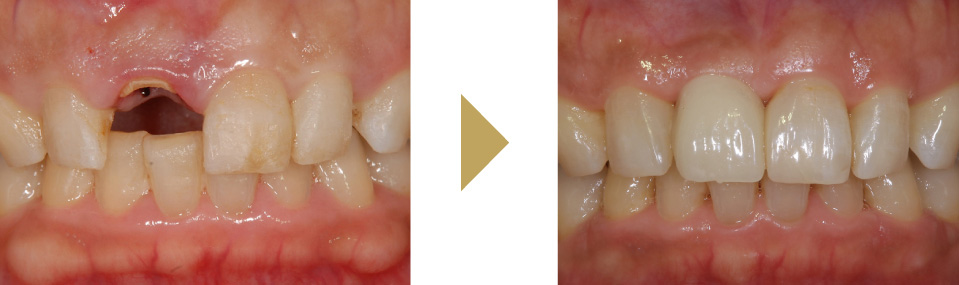

インプラント

インプラントは、失った歯の部分の骨にチタン製のネジを植え込み、その上に歯の被せ物を乗せる構造をしています。

インプラントの一番の特徴は、入れ歯やブリッジと違い他の歯に迷惑をかけないところです。入れ歯の様に健康な歯にフックをかけたり、ブリッジの様に前後の歯を削らなくて済むので長い目で見ると一番周りの歯に優しく、長持ちすることが論文でも証明されています。 また、本来の歯の形と同じ形状大きさをしているので、異物感もなく自分の歯の様に噛むことが可能です。 |